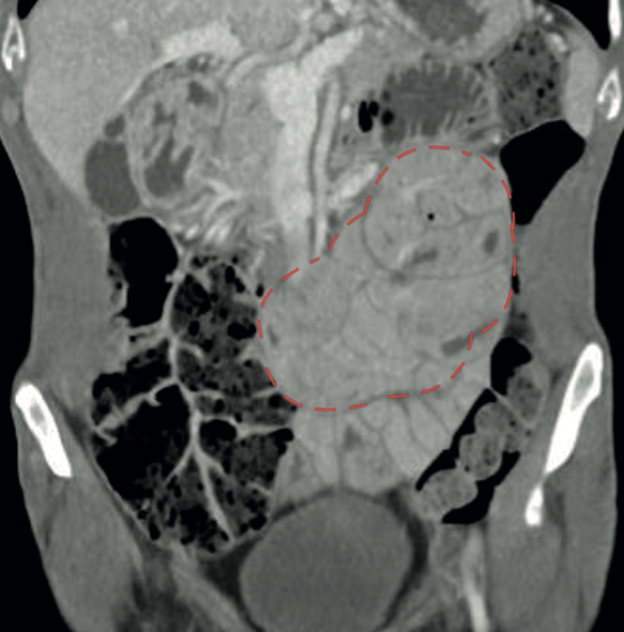

Resultados: Se presentan 4 pacientes masculinos, ingresados por dolor abdominal, vómitos y baja de peso. El 75% tuvo diagnóstico preoperatorios por tomografía computada (TC), mostrando obstrucción duodeno-yeyunal con dilatación duodenal y gástrica. Se confirmaron diagnósticos mediante biopsia postquirúrgica. La intervención fue abierta, con adherenciolisis y resección de cápsula fibrosa. Se logra un 100% de seguimiento con hasta 17 años del primera caso. Un paciente presentó obstrucción intestinal a los 9 años de seguimiento, la mayoría recuperó peso y mejoró su calidad de vida.

Discusión: La PEE se caracterizada por una membrana fibrocolágena que envuelve el intestino delgado, causando obstrucción. Sus síntomas son inespecíficos, destacando pérdida de peso, vómitos y dolor abdominal. El manejo es quirúrgico, con resultados adecuados y un perfil de complicaciones aceptables, dado lo infrecuente de la condición esta serie es posiblemente la más grande presentada a nivel nacional con seguimiento a largo plazo.